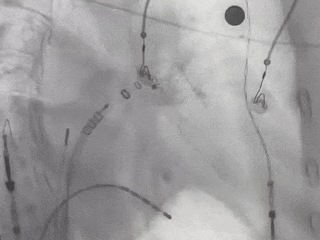

封堵前多角度进行造影确认缺损

肝位造影

右肩位造影

输送左心耳封堵器

排气

输送封堵器

ICE下输送封堵器